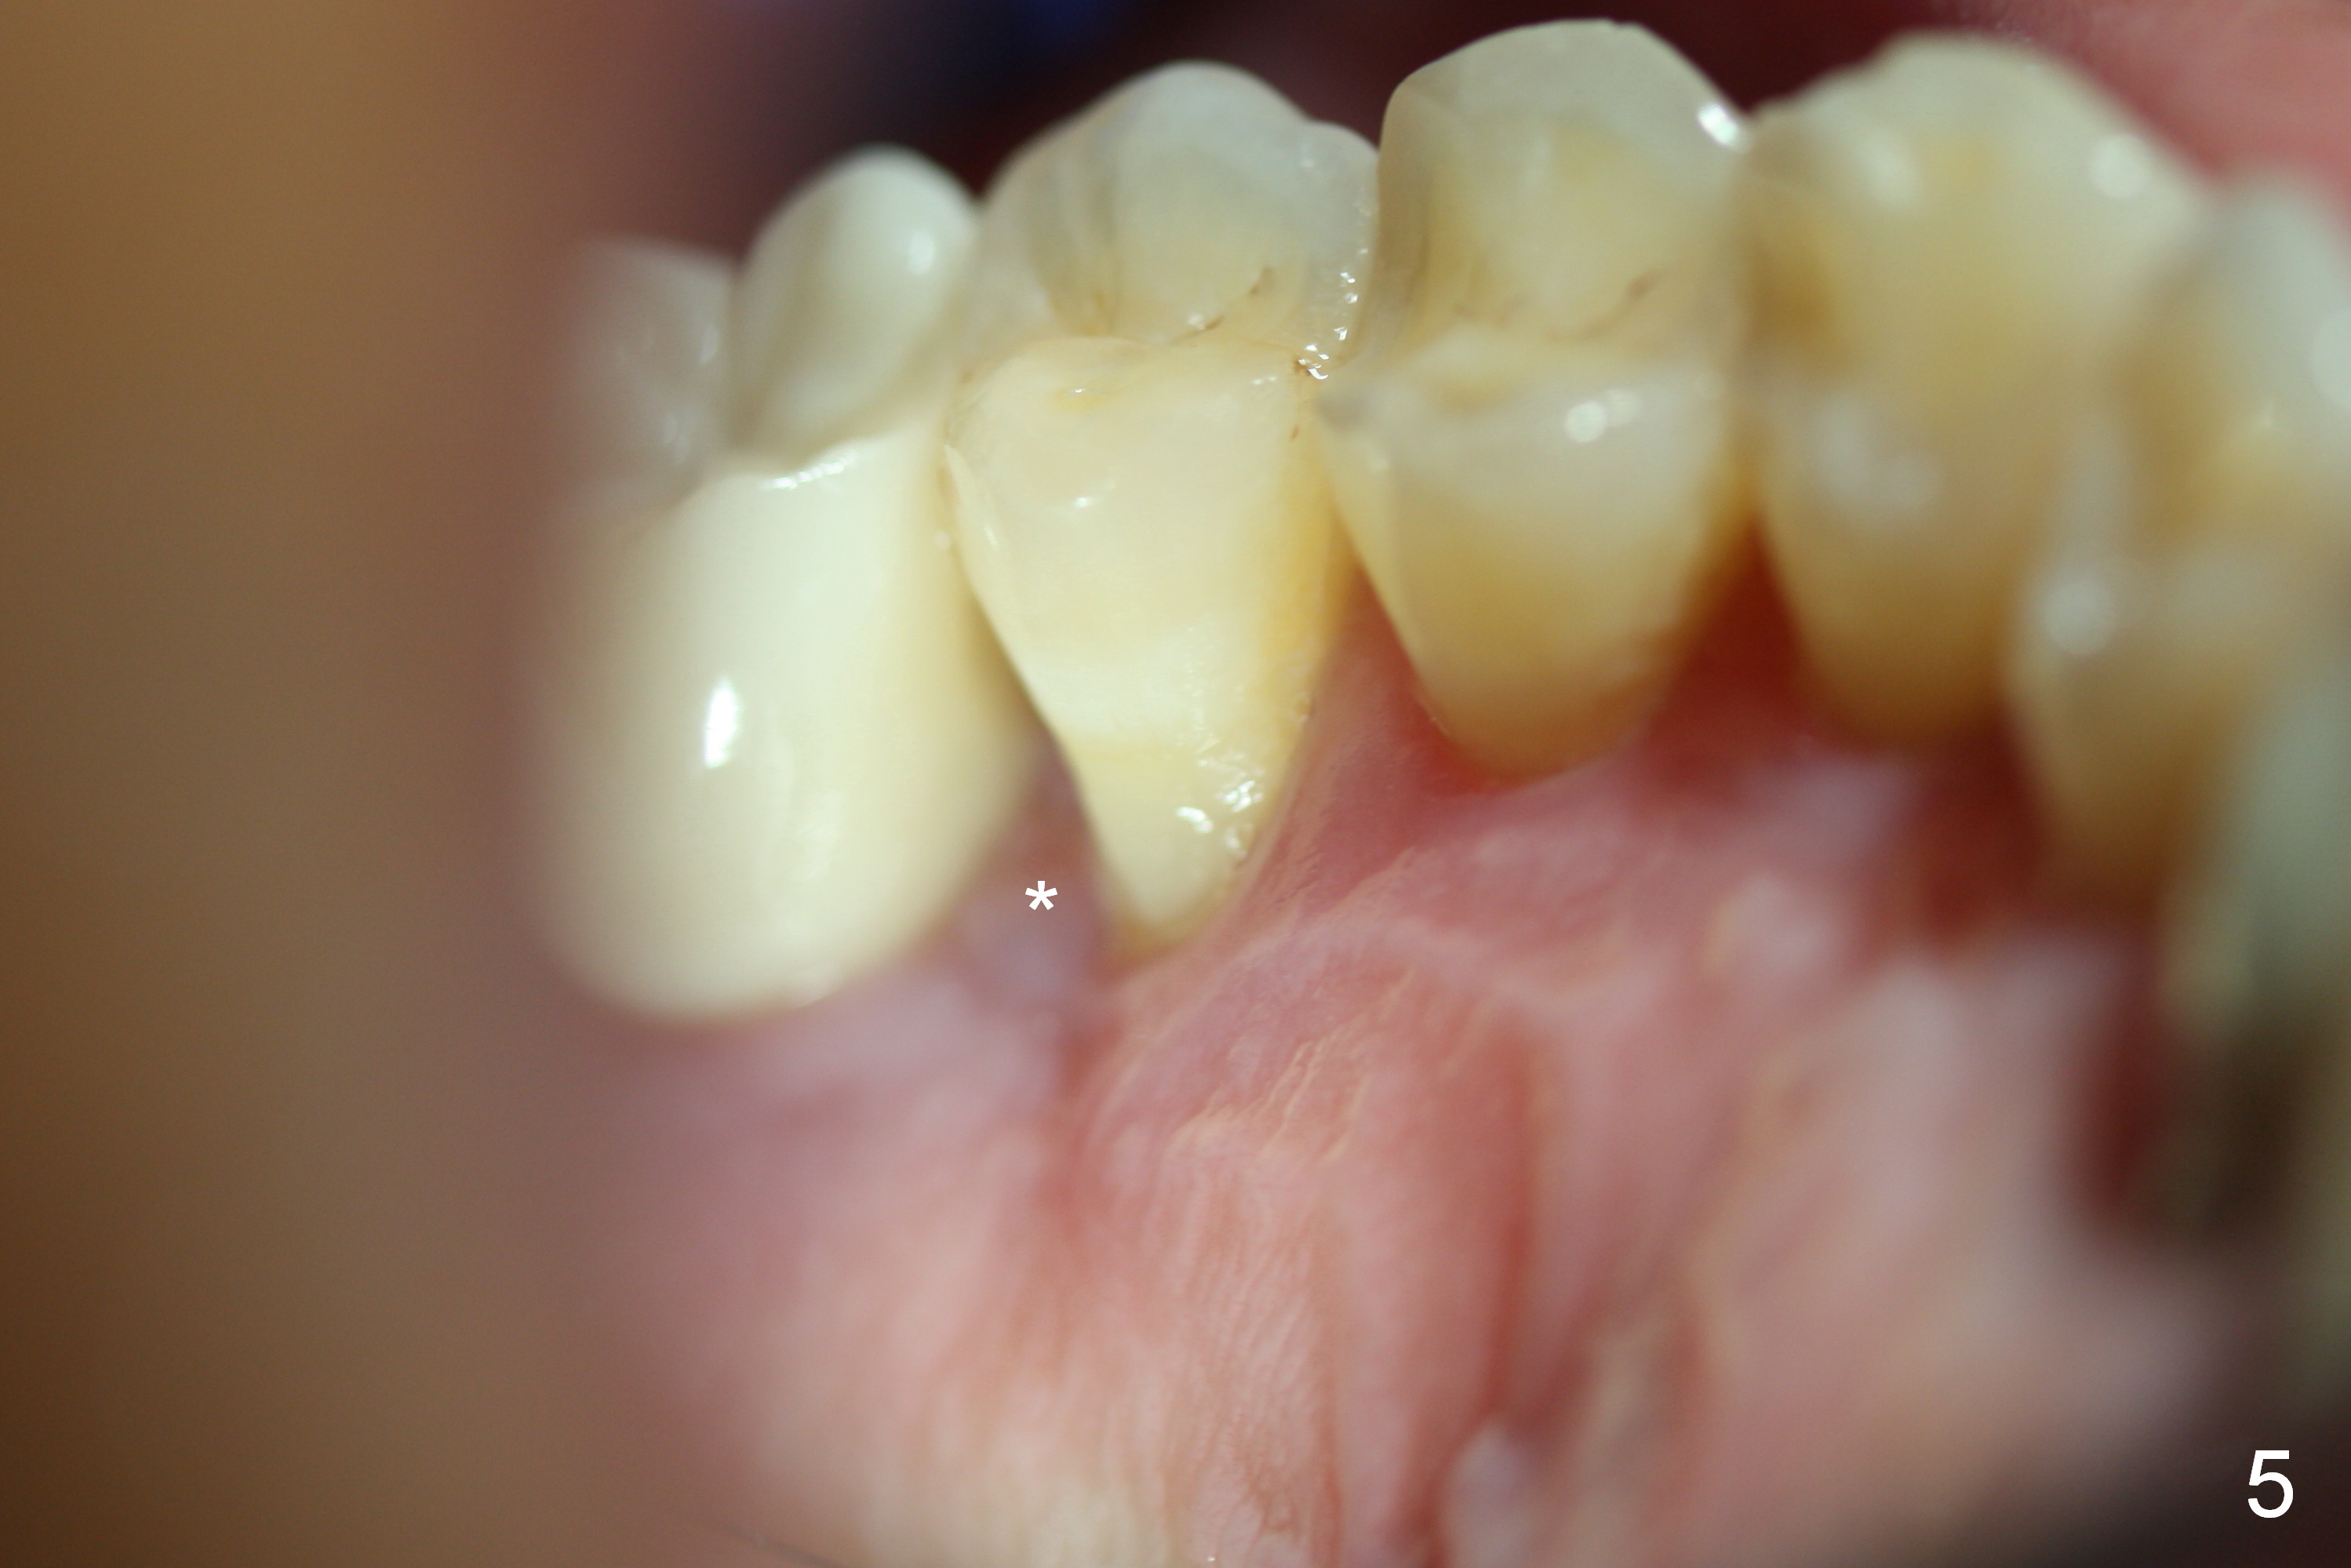

The distal papilla reforms buccally (Fig.8 *) and palatally (Fig.9) 4 months postop.  It appears that the 4 mm cuff of the pair abutment (Fig.10 >) is apical to the mesial crest (*).  The distal coronal implant threads seem to be covered by bone graft (Fig.11 <).  Therefore pair abutments with 5 mm or more cuff are required in cases of the uneven bone.   Implants have to be placed deep.  CT taken 3 months post cementation (10 months postop) shows that the implant is placed in the middle of the alveolus without apparent thread exposure.  CT taken 1 year and 8 months post cementation (Fig.13) shows that the implant is placed in the middle of the alveolus without apparent thread exposure, as compared to those at #2 and 3, which are placed buccal (B).